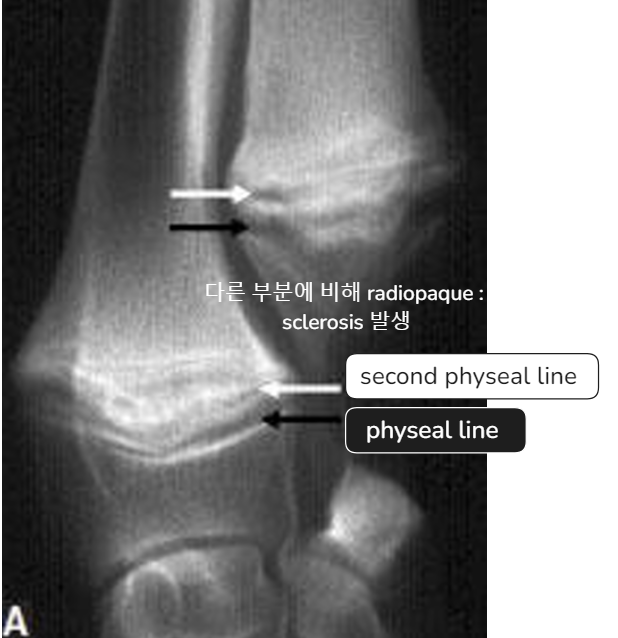

| - ์๋์ชฝ๋ง ์์์ผ๋ก ์ปค์ง๋ฉด์ flaring ์์์ ๋ณด์. | Early sign - Metaphyseal soft tissue swelling | ๋น์ ์์ ์ธ periosteal reaction์ด ์ฌํ๊ฒ ๋ํ๋จ, ์ฑ์ฅํ๋ ์์ ๋ฐ์ |

- Physeal line์ ์์์ด ์ฌํด ๊ฐ๊ธฐํ? ๋ฑ ๋ฌธ์ ๊ฐ ๋ ์ ์์.